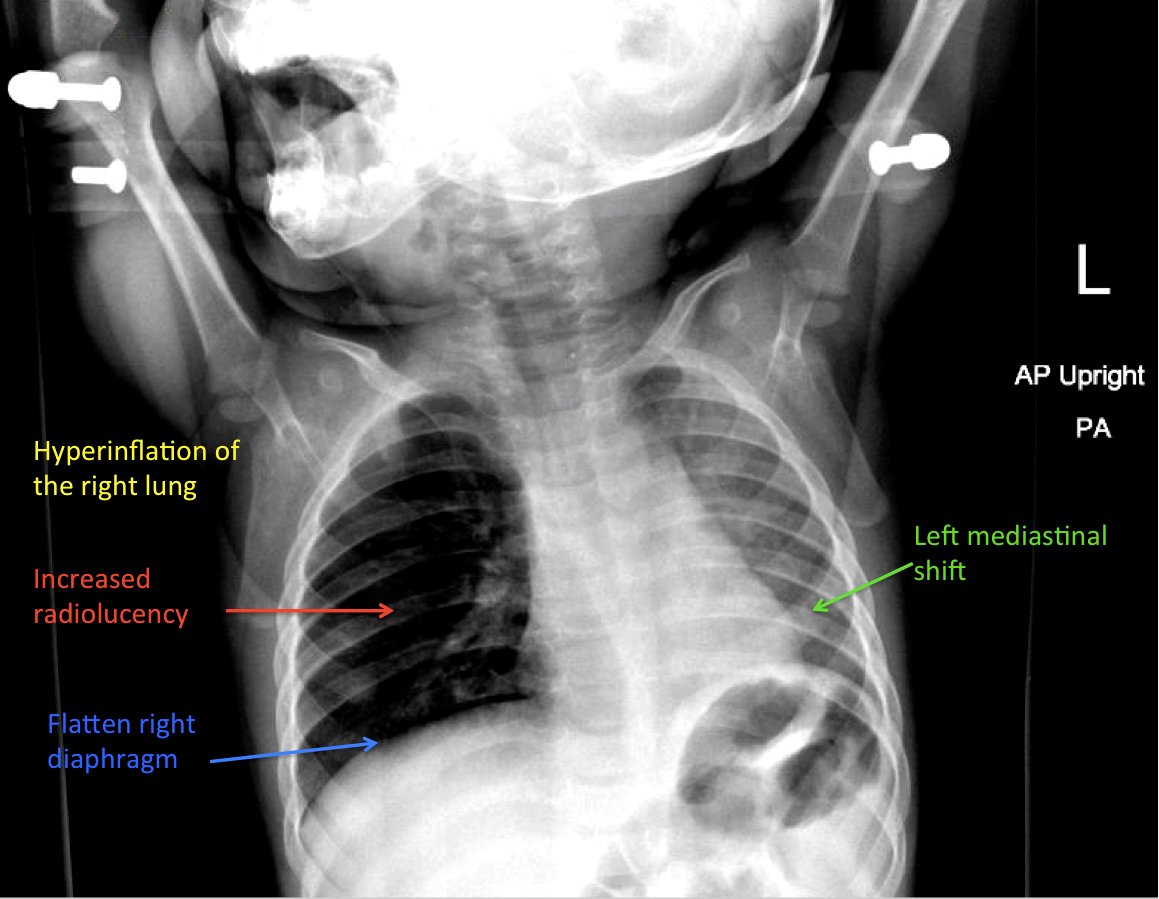

Chest radiograph showed increased radiolucency (red arrow) and flattening of the diaphragm on the right side (blue arrow) consistent with hyperinflation of the right lung, as well as left mediastinal shift (green arrow), indicating obstruction.

Chest radiographs are excellent in detecting radiopaque objects. However, most aspirations are from radiolucent organic matters such as nuts or seeds.3 Radiographs that show focal area of hyperinflation, mediastinal shift, and atelectasis are highly specific for aspiration. Pathological findings on chest radiography showed an 86.1% sensitivity and 63.2% specificity.3 However, it is possible that these finding may not be seen on initial imaging.